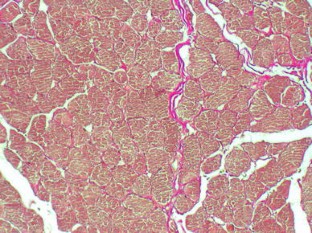

Ionizing radiation as a cancer therapy is associated with a variety of undesirable side effects. Consequently, radiotherapy can negatively affect neuromuscular function. Clinical observations have identified problems with swallowing and voice function. Our study aims to evaluate the impact of radiotherapy on laryngeal soft tissues using image analysis to quantify its effect on the structure of the vocalis and thyroarytenoid muscles. Case control study, retrospective analysis. We collected total laryngectomy specimens from six patients with persistent or recurrent cancer who had received preoperative radiotherapy (60–66 Gy). The control group consisted of total laryngectomy specimens from six patients who underwent surgery as primary treatment. Sampling of the specimens only included non-cancerous laryngeal tissue. Laryngeal histological slices were evaluated using digital morphometric analysis system. Percentage of fibrosis and density of muscle fibers within the thyroarytenoid muscle were evaluated in both groups. We found no significant quantitative differences in muscle fibrosis (7.92% vs. 7.52%, P > 0.1). Changes were rather qualitative and included changes in the organization of the muscular fibers. A significant reduction in muscle fibers, however, was observed in the samples from irradiated larynges (66.45% vs. 42.03%, P < 0.01). Our analysis suggests that radiotherapy is responsible for a significant reduction in muscle fibers in the thyroarytenoid muscle and that these changes occur during treatment or relatively early after its completion. Loss of muscle mass after irradiation correlates with clinical observations of muscle weakness and decreased function in patients who undergo radiotherapy.

Fig. 2